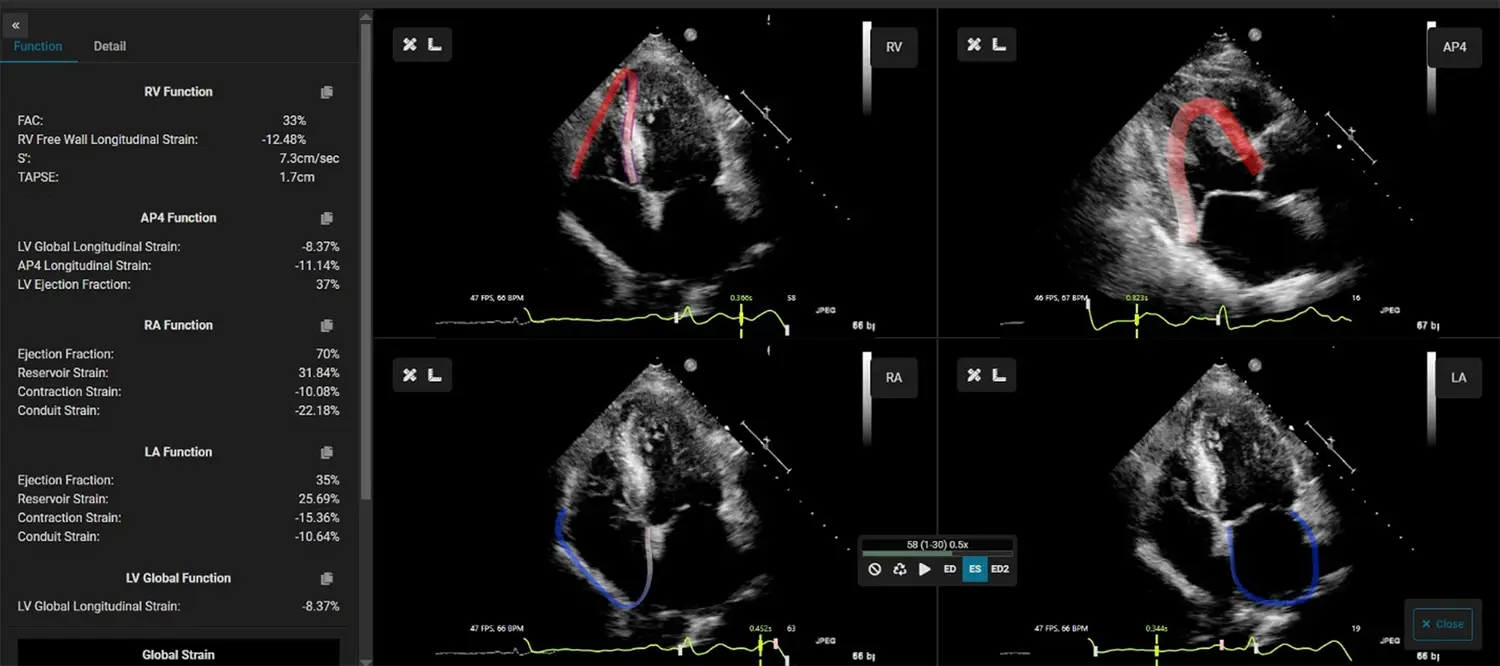

EchoInsight® Zero Footprint with AutoAssist™ is an offline, vendor-neutral, zero-footprint, zero-click echo analysis platform that runs from a single server.

Leverage EchoInsight® ZF to integrate advanced echo analysis into your routine practice.